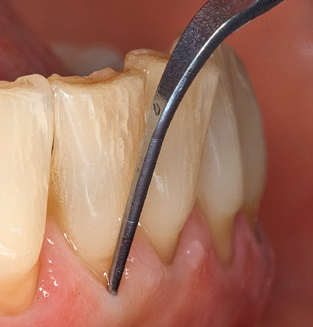

Following machine cleaning of the tooth and implant surfaces, the surfaces of the natural teeth are cleaned manually using standard hand instruments. When performing manual cleaning, particular attention must be given to maintaining the correct angle of application, appropriate sharpness, good support and working with the curette from apical to coronal. Either titanium or carbon curettes should be used for post-cleaning of the implant structures (Fig. 8). In addition to the use of ultrasonic devices, power jet devices can also be used in conservative dentistry. However, it must be taken into consideration that these procedures are not suitable for removing hard deposits and thus they cannot replace the use of hand instruments and ultrasonic instruments completely. In all cases, cleaning is followed by mechanical polishing of the accessible tooth and implant surfaces with polishing cups and polishing compounds (Fig. 9).

Fig. 4: Flexible probes with millimetre markings are recommended for the probing of dental implants (e.g. Colorvue Kit PCV11KIT6, Hu­Friedy). – Fig. 5a and b: A straight working tip (1P, W&H Dentalwerk Bürmoos GmbH) is a suitable instrument for use on all natural teeth. – Fig. 6: Curved working tips (3Pr/3Pl, W&H Dentalwerk Bürmoos GmbH) lend themselves to the processing of difficult-to-reach areas of the tooth and root surfaces (e.g. furcations). – Fig. 7: The tapered, hexagonal implant cleaning tip (1I, W&H Dentalwerk Bürmoos GmbH) permits atraumatic and efficient cleaning of the crown and abutment surfaces. – Fig. 8: Titanium and carbon curettes are suitable instruments for the manual cleaning of the implant surfaces.